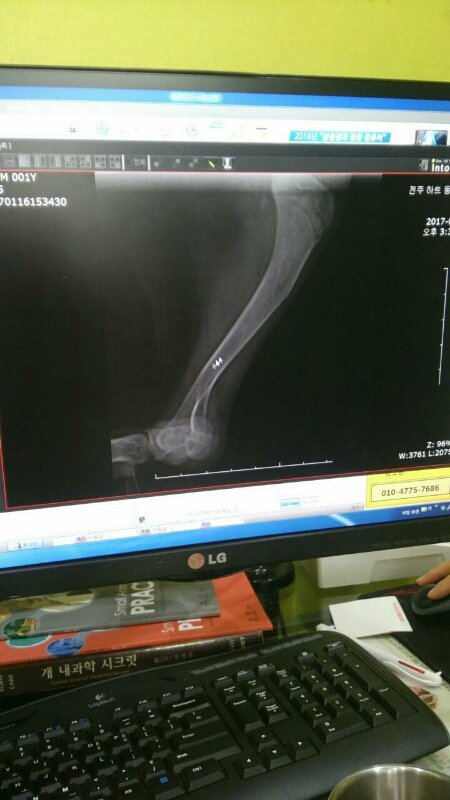

블리는 약 한달전 교통사고를 당한 아이를 주인으로 추정되는 사람이 데리고는 왔지만 아이 상태 문제로 연락을 취했지만 현재 연락이 두절된 상태라고 합니다.

오랜시간 다친 다리에 치료를 진행하지 못해 병원에선 불가피하게 절단을 선택하게 되었고 어린 아이는 그 힘든 수술도 잘 견뎌 내주고 좁은 공간이지만 병원안 한켠이 자신의 공간이라 생각하면서 그곳을 만족해하며 세발로도 베시시 사람이 좋다 먼저 다가가 웃는 모습에 그저 마음이 아프기만 합니다.